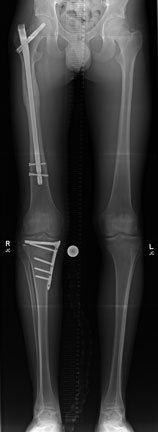

So we carried out quite a complex operation. Firstly, we fixed his femur with a long 'nail' - you can see that on the left side (your left) of this long-leg X-ray, Then we turned him onto his tummy and opened up the back of his knee. Here we located the bits of bone still attached to the PCL and put them back on again (which is called a primary repair of the ligament). Then turned him onto his side and repaired all the ligaments on the outside.

However I wasn’t happy with the PCL repair so once he recovered from his femoral fracture, I took him back to theatre and carried out an osteotomy to valg-ise him. At the same time I increased his tibial slope in order to improve his PCL deficiency and resultant knee instability. I was expecting to tee him up for a revision PCL reconstruction, but as is so often the case, by increasing his slope in a sagittal plane and making it steeper, we corrected the fact that his PCL is not that great and on his follow-up appointment he was very happy with the results of his surgery and was not complaining of any instability.